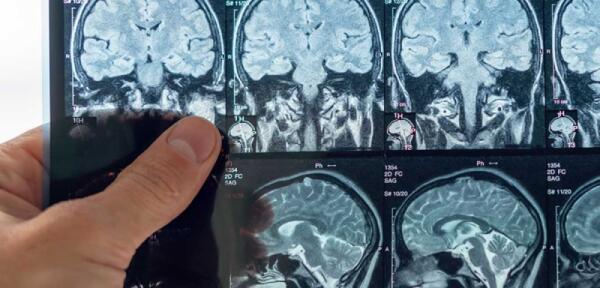

Tumori cerebrali primitivi: attualità, nuovi trattamenti e prospettive future

26 novembre 2025 15:35